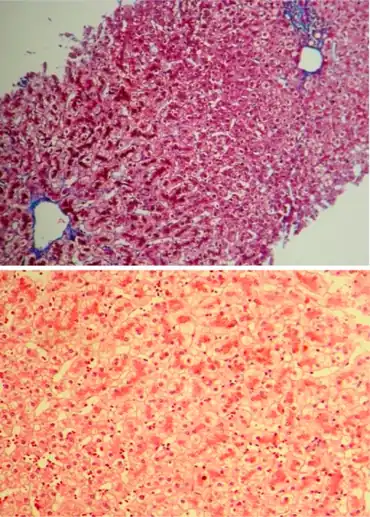

It is inherited as autosomal recessive, and causes an isolated increase of conjugated bilirubin in the serum.[5] The liver typically appears black due to the deposition of a pigment similar to melanin.[5] This condition is associated with a defect in the ability of hepatocytes to secrete conjugated bilirubin into the bile, and is similar to Rotor syndrome.[5] It is usually asymptomatic, but may be diagnosed in early infancy based on laboratory tests.[5] No treatment is usually needed.[5]

In post mortem autopsy, the liver will have a dark pink or black appearance due to pigment accumulation.